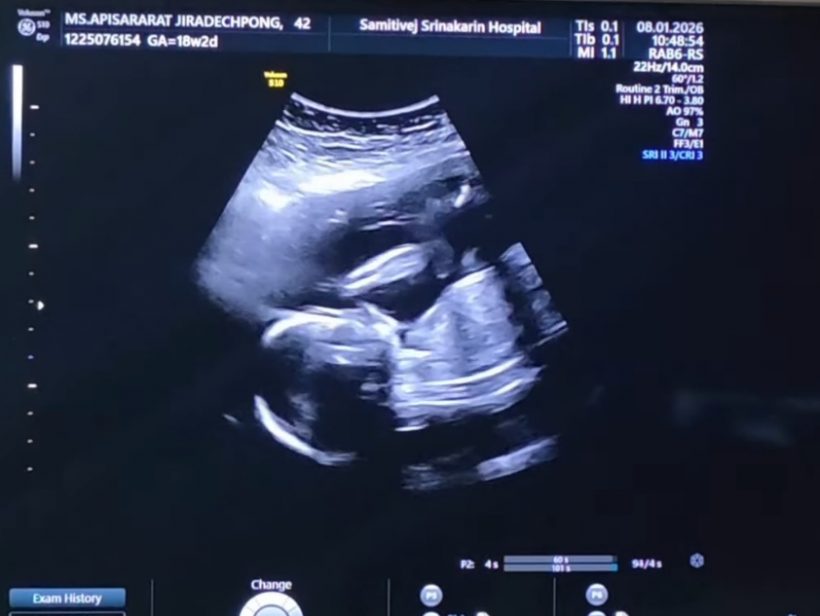

ล่าสุด ลีซอ โพสต์อินสตราแกรม @leesawls14 เผยโมเมนต์อัลตร้าซาวด์ลูกน้อยในครรภ์ภรรยา พร้อมแคปชั่นระบุว่า "รอวันพบกันนะลูกนะ #18w2d #LFbaby"